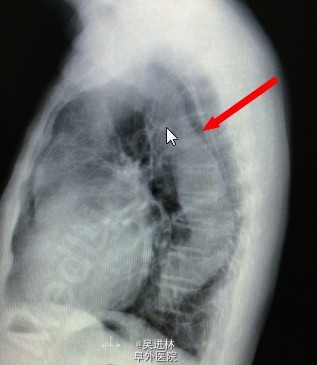

患者男,68岁,因“发现主动脉关闭不全11年”入院。患者11年前因头晕,就诊与当地医院,心脏超声提示:主动脉瓣关闭不全。后患者逐年复查,未行特殊治疗。1周前患者来我院就诊,超声提示:二叶瓣畸形,主动脉瓣重度狭窄办重度关闭不全,主动脉窦部及生主动脉增宽,未行手术入院。

诊断: 主动脉瓣二叶瓣畸形 主动脉关闭不全 主动脉窦部及生主动脉增宽 心脏扩大 心功II级 高血压病2级(极高危) 处理:手术换瓣bental

正常的主动脉瓣共有三个瓣膜。心脏收缩时,三个瓣膜同时打开,血液由左心室进入主动脉;心脏舒张时,三个瓣膜协同关闭,防止血液从主动脉返流入左心室。若主动脉瓣先天性只有两个瓣膜,称为主动脉瓣二瓣化畸形,是最常见的先天性主动脉瓣狭窄畸形。由于瓣叶结构异常,长期受到血流的不断冲击,易引起瓣膜增厚、钙化、僵硬、纤维化,最终导致瓣膜狭窄。这样会引起体循环灌注不足,头晕,乏力,心绞痛。更关键的,由于血流动力学改变,常常导致主动脉根部瘤样扩张。